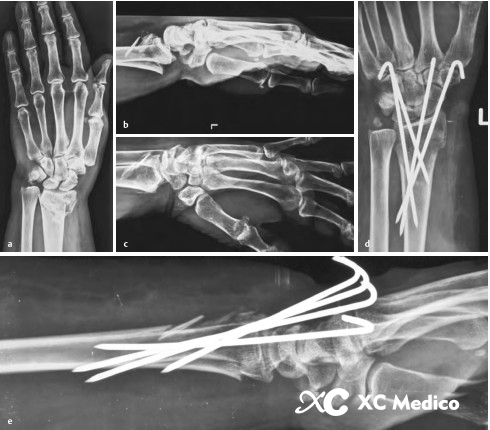

4. Когда дорсальная кора чрезвычайно заправлена, постарайтесь не войти в место разрушения фрагмента дистальной кости, так как это может привести к неудаче фиксации. Рисунки AE ниже.

5. Для тяжелого остеопороза лучше всего использовать провода от четырех до пяти киршнеров, чтобы исправить перелом. Иногда, чтобы поддерживать длину радиуса, поперечная проволока Киршнера используется для исправления дистального радиуса костяного блока до дистальной локтевой кости.

6. В длинных переломах сегмента эпифизарного конца можно использовать большую наклонную проволоку Киршнера. Тем не менее, проволока Киршнера может проскользнуть в медуллярную полость, и его трудно исправить (рисунки AD ниже).